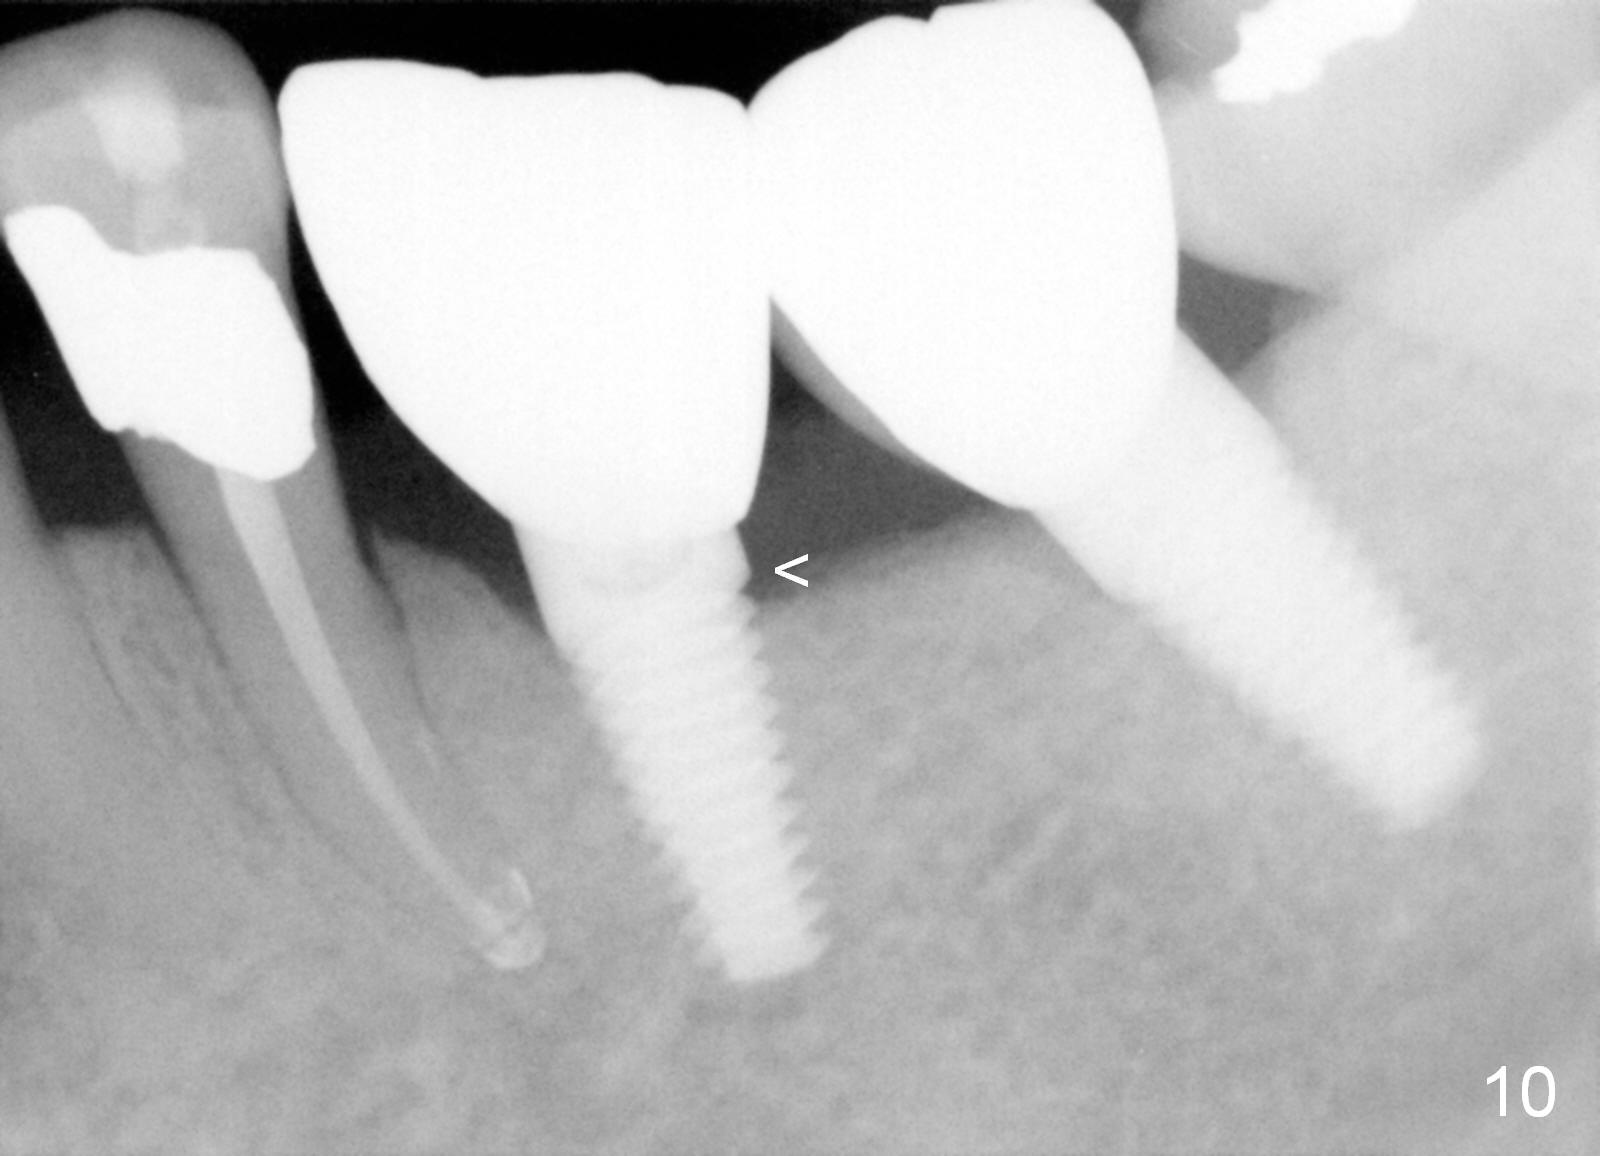

Three months postop, crestal bone has started to resorb (Fig.9 arrowheads).  Resorption gets worse over time (Fig.10: 4 months post cementation, 11 months postop) (Fig.11: 1 year 2 month post cementation).  On the other side (#30), postop bone resorption is not so severe.  The patient's main concern is that she does not have normal taste ever since she got the implants.